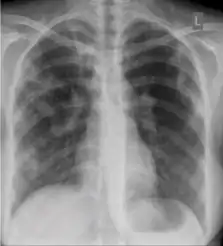

Chest X-ray

A posterior-anterior (PA) chest X-ray is the standard view used; other views (lateral or lordotic) or CT scans may be necessary.

These are films that are completely normal, with no identifiable cardiothoracic or musculoskeletal abnormality.